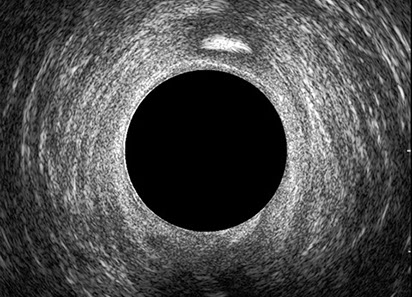

L’ecografia transanale è un esame diagnostico per immagini che consiste nell’introduzione di un trasduttore ad ultrasuoni. Le immagini qualitativamente migliori del canale anale sono ottenute usando un trasduttore rotante, montato in un manipolo rigido, che fornisce un’immagine a 360°. Con le apparecchiature più moderne è anche possibile ottenere immagini tridimensionali.

L’ecografia transanale permette di distinguere la sottomucosa che riveste il canale anale, lo sfintere anale interno, e lo sfintere anale esterno.

Le principali indicazioni all’esecuzione di tale esame sono lo studio dell’integrità delle strutture muscolari nei casi di incontinenza fecale, lo studio topografico dei processi settici perianali (ascessi e fistole) e lo studio dei processi proliferativi epiteliali (carcinoma anale).

Proctal dispone di apparecchiatura per ecografia endoanale 3D con sonda rotante.